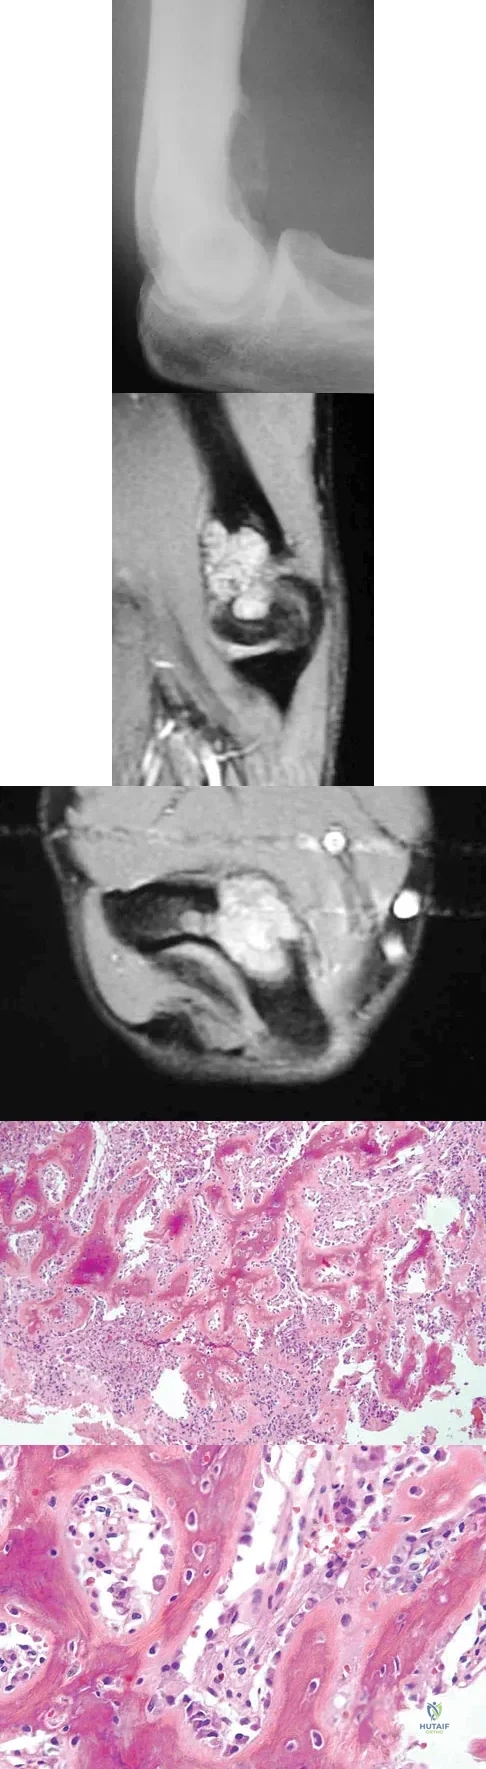

Question 55 High Yield

A 17-year-old boy has had elbow pain for the past 6 weeks. A radiograph, MRI scans, and biopsy specimens are shown in Figures 65a through 65e. What is the most likely diagnosis?

Detailed Explanation